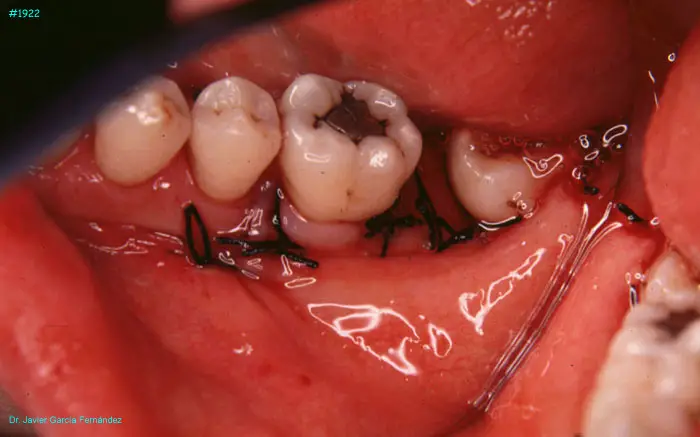

image 69